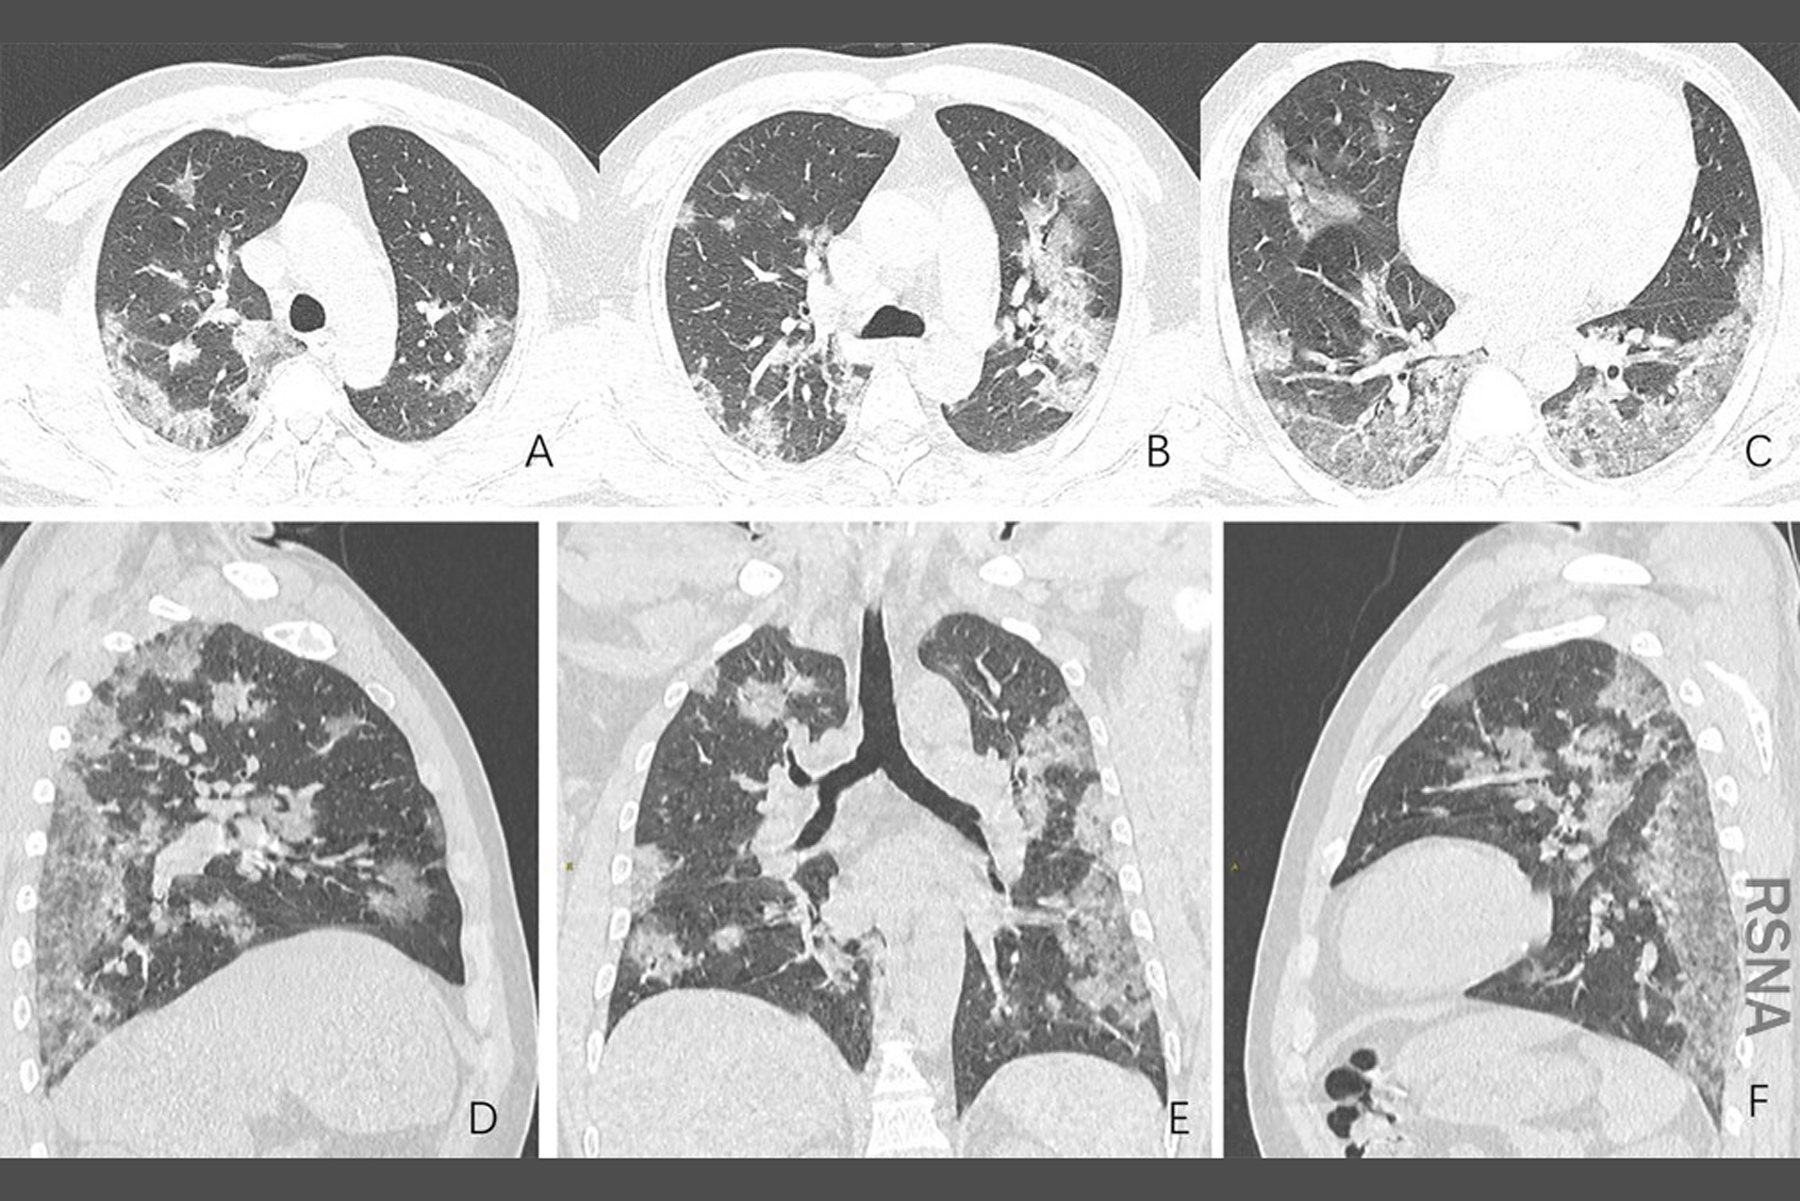

폐손상이 있게 되면 폐조직 자체는 회복이 이전처럼 당연히 될 수 없기 때문에 호흡기계 장애가 남을 수 있지만

코로나 바이러스에 걸린 사람들의 후유증은 다른 여러가지 증상이 있으며, 다른 증상들도 증상이 오래 남는다고 합니다.